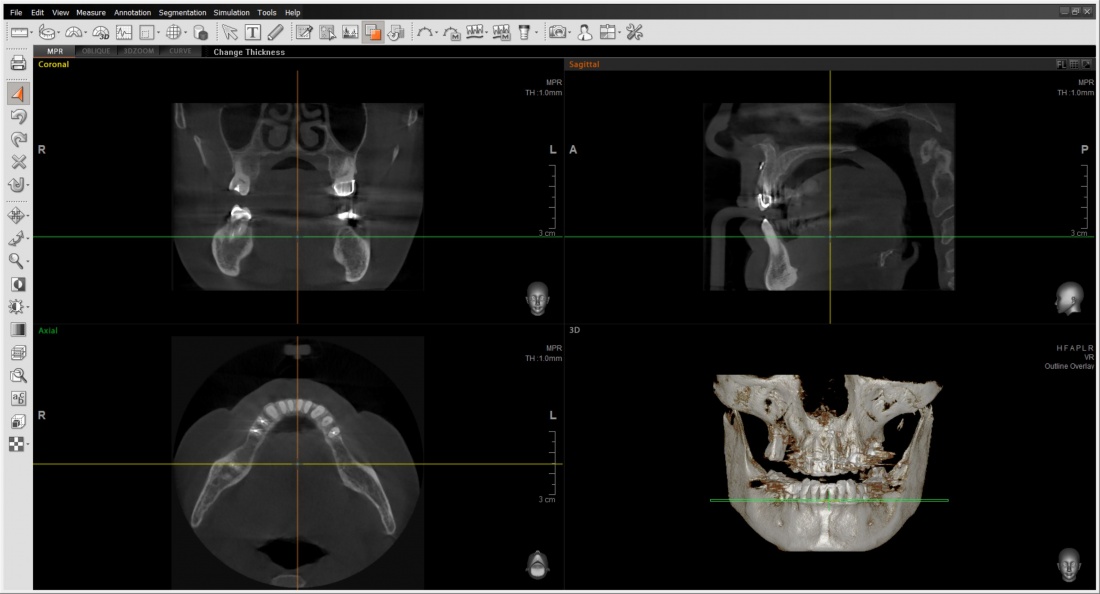

Для этого мы сделали КЛКТ:

И КЛКТ показала нам, что с имплантатами и окружающей костью всё зашибись. Через 12 лет после операции, отсутствия наблюдения, пофигизма в замене временных коронок! Нужны ли тебе еще какие-нибудь доводы в пользу долгосрочной эффективности метода?